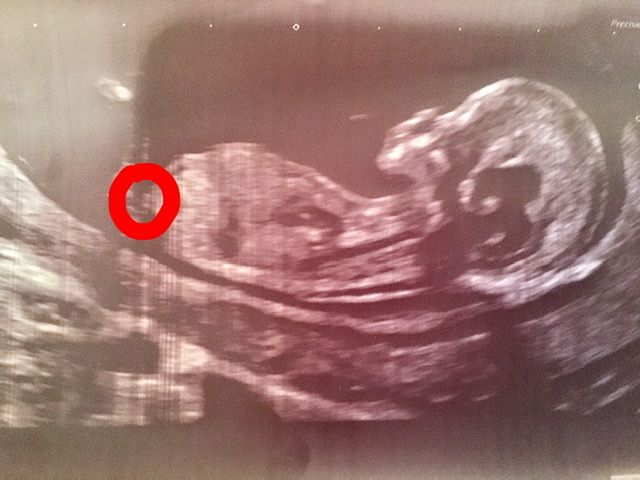

Hi, this is the best image from my scan yesterday. During scan I thought I saw nub - long bright white line - but couldn’t work out angle. Unfortunately, it’s not in the picture - but I wondered if the two tiny lines circled might be the end of it poking out? If so, could anyone hazard a guess as to sex? Thanks in advance!